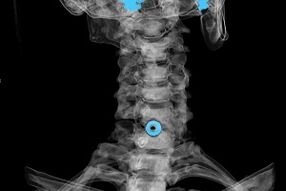

The diagnosis is established based on characteristic symptoms, in addition to:

- X-ray. The method is ineffective, especially in the last stages of the development of osteochondrosis.

- Magnetic resonance imaging (magnetic resonance imaging) of the cervical spine.A method that allows you to see bone structures, intervertebral disc hernias, their size and direction of development.

- Computed tomography.A less effective solution than MRI, as the presence and size of hernias are difficult to determine.